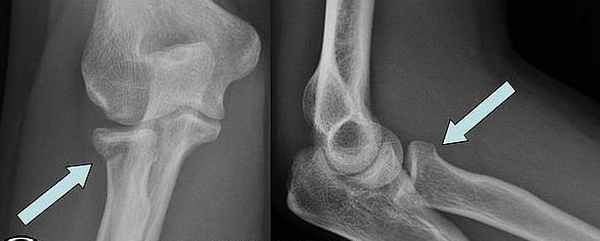

Перелом локтевой кости с вывихом головки лучевой кости (перелом Монтеджа) • Причины: падение на руку, отражение удара поднятым вперёд и вверх согнутым под прямым углом предплечьем • Патоморфология. Различают сгибательный (головка лучевой кости смещена кпереди, отломки локтевой кости — кзади; образуется угол, открытый кпереди) и разгибательный (головка лучевой кости вывихнута кзади и кнаружи, отломки локтевой кости смещены кпереди; образуется угол, открытый кзади) переломы • Клиническая картина. Характерная деформация (западение со стороны локтевой кости и выбухание со стороны лучевой), укорочение конечности, обнаружение при пальпации перелома локтевой и вывихнутой головки лучевой костей, отсутствие активных движений, боль и пружинящее сопротивление при пассивном сгибании. Возможно повреждение лучевого нерва. Необходима обязательная рентгенография с захватом локтевого сустава и области перелома • Лечение •• Сгибательный перелом — репозиция и вправление вывиха в положении разгибания, фиксация конечности в положении разгибания руки и супинации предплечья на 6–8 нед. При невозможности одномоментной репозиции — оперативное вправление вывиха и остеосинтез •• Разгибательный перелом — репозиция и вправление вывиха в положении супинации, гипсовая повязка (4–5 нед в положении супинации, 4–6 нед в среднем положении между супинацией и пронацией). Оперативное лечение при невозможности одномоментной репозиции (разрыв кольцевидной связки, интерпозиция мягких тканей).

Переломы Монтеджи - проксимальные переломы локтевой кости с вывихом головки лучевой кости.

Вывих головки лучевой кости легко пропустить при переломах Монтеджи, поскольку перелом настолько очевиден, что, в случае выявления перелом проксимального отдела локтевой кости, его необходимо особенно тщательно обследовать. Головка лучевой кости, как правило, видна за пределами ее нормального сочленения с головкой плечевой кости (capitulum). При переломах Монтеджи радиокапителлярная линия (линия, соединяющая шейку лучевой кости и головку плечевой кости), также не выровнена правильно, что указывает на вывих (см. рисунок Передняя плечевая линия и радиокапителлярная линия Передняя плечевая и радиокапителлярная линии ). Если при переломах Галеацци (аналогично переломам Монтеджи) есть перелом дистального диафиза лучевой кости, то легко пропустить вывих дистального лучелоктевого сустава, поэтому на него следует обратить особое внимание.